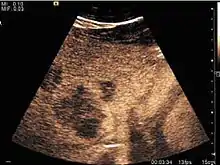

Liver cyst

Hydatid liver cyst. Diagnostic criteria are the presence of membranes and sediment inside.